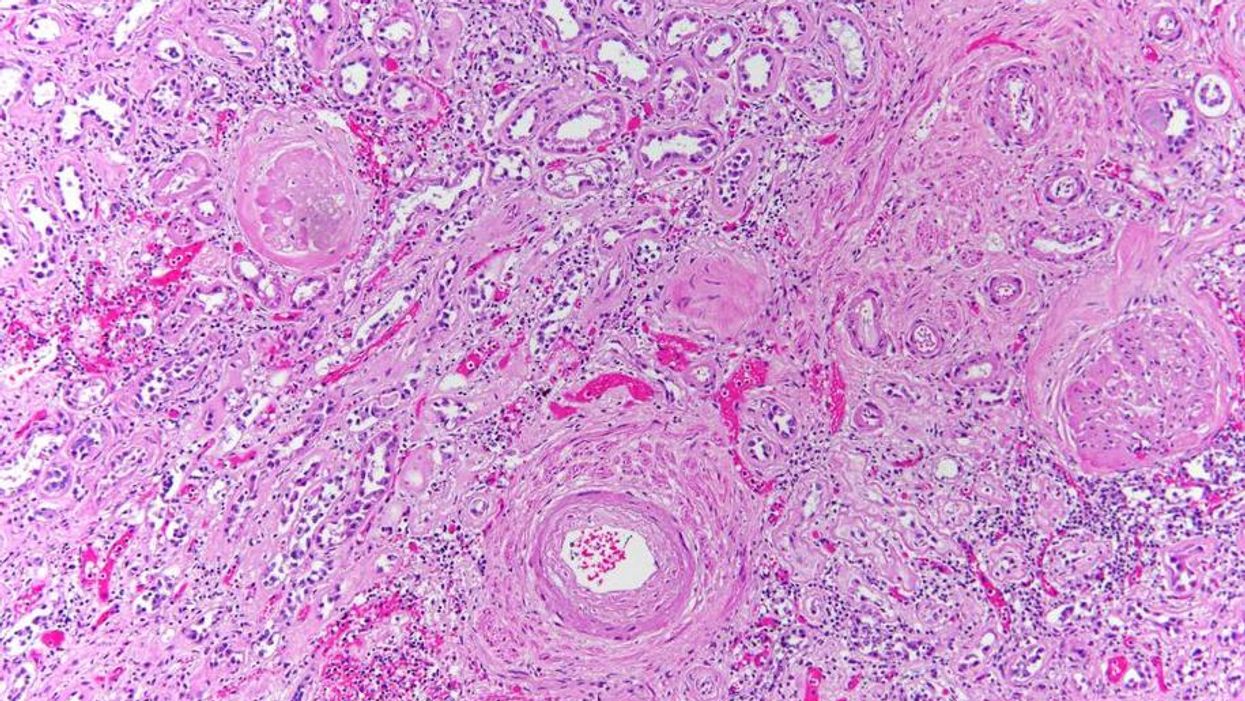

I really like looking at kidneys under the microscope. There’s part of the kidney that would make incredible wallpaper.

The kidney

The majority of the images are representative of what Dr Hamel sees when performing autopsies. The colours are diagnostic colours which are added to slides to help define human tissue.